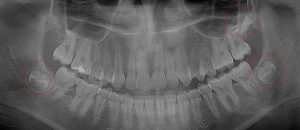

This 34 year old patient has all four third molars present (circled) and fully erupted into occlusion. They appear disease free…but are difficult to keep clean. 3rd molars are the most likely teeth to decay or have gum disease with a >98% probability that decay and gum disease will occur around all four teeth over this patient’s life time.